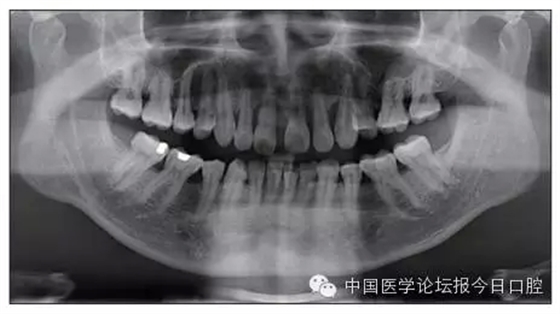

本病例為慢性牙周炎致前牙漂移、深覆(牙合)患者。本病例采用無托槽隱形矯治技術進行治療。無托槽隱形矯治器具有可摘戴、便于口腔衛(wèi)生維護和牙周治療的優(yōu)點,更適合于伴有牙周炎的錯(牙合)畸形患者的治療。 患者男,48歲,前牙有縫、前突求診。 患者面部對稱,側(cè)面觀上頜前突,下頜后縮。 口內(nèi)情況:恒牙列,24、34、44缺失,磨牙Ⅲ類關系,上牙列散隙,上前牙扇形漂移。前牙深覆(牙合)、深覆蓋??谇恍l(wèi)生較差,11與12間牙齦乳頭紅腫,多個牙探診有牙周袋形成,11松動Ⅰ度,余切牙松動(-),患者面像及口內(nèi)像如圖1、2所示。 圖1 治療前面像 圖2 治療前口內(nèi)像 全口曲面體層片(圖3)顯示,患者全牙列牙槽骨吸收;根尖片(圖4)示11近中牙槽骨角形吸收已達根尖1/3,21牙槽骨嵴頂吸收至根1/2,23牙槽骨近中骨板角形吸收至根1/2。磨牙區(qū)骨嵴頂吸收3mm。治療前頭顱側(cè)位片見圖3,治療前ODS模型見圖5。 圖4 治療前根尖片 圖5 治療前ODS模型 牙型:安氏Ⅲ類。骨型:Ⅱ類。面型:上頜前突,下頜后縮。 問題列表為:①上牙列間隙;②上切牙病理性牙移位;③前牙深覆(牙合)、深覆蓋;④24、34、44缺失;⑤慢性牙周炎。 矯治目標包括:①排齊牙列,關閉牙列間隙;②改善前牙深覆(牙合)、深覆蓋;③改善牙周狀況。 矯治設計有:①牙周基礎治療與維護。②壓低、內(nèi)收上切牙,關閉上牙列間隙。③壓低下切牙,伸長下后牙,整平Spee曲線,改善前牙覆(牙合)、覆蓋。 患者進行全口齦上潔治、齦下刮治,口腔衛(wèi)生宣教,并按牙周醫(yī)師的要求,每2~3個月行牙周檢查與治療。 牙周基礎治療結(jié)束3個月,開始隱形矯治。于14、25、35、36、45、46上粘接附件(圖6),于16、26(牙合)面粘接(牙合)墊。 圖6 ODS設計附件粘接圖示 矯治過程中注意(牙合)墊是否脫落或磨損,及時修補。 注意上前牙內(nèi)收時有無咬合干擾,及時調(diào)(牙合)。下頜前磨牙伸長到位后,磨除16、26(牙合)墊。 下頜佩戴第24步矯治器時,分別在36、37、46、47的頰、舌側(cè)粘接舌扣,矯治器上預留伸長空間,用3/16英寸、3.5盎司皮圈牽引,輔助伸長下磨牙(圖7)。 患者共戴用矯治器上頜32步,下頜26步。 矯治后,牙列間隙關閉,面型及覆(牙合)覆蓋改善。11根尖片(圖8)顯示,治療后較治療前,牙周支持組織增加,牙槽骨角形吸收區(qū)水平向縮小0.3mm,垂直向縮小0.6mm。11松動Ⅰ度,余切牙無松動。 圖8 治療后根尖片 圖9 治療后口內(nèi)像 圖10 治療后X線檢查 圖11 治療后ODS模型 正畸-牙周聯(lián)合治療對于牙周組織的影響 多學科綜合治療牙周炎患者不再是正畸治療的禁忌證。良好的牙周治療為正畸治療中的牙齒移動打下堅實基礎,而正畸治療排齊牙齒、去除(牙合)干擾,有利于牙周健康。 牙周炎患者的正畸治療必須在牙周炎癥得到控制后才能進行,否則,菌斑會隨著牙齒的移動,特別是壓低而使牙周炎癥加重。牙周炎的正確診斷、牙周炎癥控制、正畸治療中和治療后的認真維護是治療成功的關鍵。根據(jù)臨床需要,一般每2~4周做一次潔治,每3個月進行牙周評估,同時患者必須進行非常良好的日??谇恍l(wèi)生維護。 固定矯治器使得牙周檢查、潔治和日??谇恍l(wèi)生維護變得困難,隱形矯治器可自行摘戴,便于患者日常維護和牙周治療,節(jié)約時間,提高菌斑控制效果。 有臨床研究表明,對于存在(牙合)創(chuàng)傷,伴有角形吸收的患牙,經(jīng)過牙周翻瓣手術控制住牙周炎癥后,使用正畸輕力壓低患牙,可以改善牙槽骨吸收的程度,并獲得一定程度的牙周新附著。本病例切牙壓低后,原來的牙槽骨吸收有改善。 病理性牙移位 病理性牙移位(PTM)在重度牙周炎患者中的發(fā)生率為30%~50%,且常見于上前牙區(qū)。其主要由于牙周支持組織喪失尤其是骨組織的丟失,咬合因素(如后牙缺失、前牙深覆牙合、牙合創(chuàng)傷等),頰舌唇肌力量不平衡及牙周和根尖周組織炎癥所致,是牙周炎患者要求正畸治療的主要原因之一。 PTM須通過正畸、牙周聯(lián)合,有時須配合修復才能達到理想的治療效果。正畸治療通常是壓低牙齒,臨床研究表明,牙周手術配合正畸壓低可以產(chǎn)生新附著,有利于PTM牙周組織的恢復。 本病例右上中切牙牙槽骨角形吸收,在盡量保證治療前后根尖片投照角度一致的情況下,以鄰牙作為校準,在根尖片上對治療前后的骨量進行評價,治療后牙槽骨角形吸收區(qū)水平向縮小0.3 mm,垂直向縮小0.6mm。盡管根尖片并不能說明骨量改變,但從影像學上能看到骨吸收區(qū)域有所減小。 無托槽隱形矯治器矯治牙周病的優(yōu)勢 無托槽隱形矯治器具有可摘戴、便于口腔衛(wèi)生維護和牙周治療的優(yōu)點,更適合于伴有牙周炎的錯(牙合)患者的治療;同時,無托槽隱形矯治器佩戴后具有牙弓夾板和(牙合)板的作用,可有效減少側(cè)向力,有利于牙周的恢復和減輕牙齒松動;由于無托槽隱形矯治器的設計是在三維數(shù)字模型上進行的,每個矯治器移動牙齒的數(shù)量和每個牙齒的移動距離可以得到量化控制,因而可以根據(jù)患者牙槽骨水平和對矯治力的耐受情況個性化設計矯治力,并且可以根據(jù)矯治中牙齒移動情況調(diào)整后續(xù)矯治器的設計。 有關磨牙伸長 單純使用無托槽隱形矯治器同步伸長后牙比較困難。該病例先使用磨牙(牙合)墊打開咬合,通過矯治器伸長前磨牙,在前磨牙建立咬合后,磨除磨牙上的(牙合)墊,通過輔助牽引伸長磨牙,最終達到伸長后牙、整平Spee曲線的目的。 史真,主任醫(yī)師,現(xiàn)任北京黃寺整形外科醫(yī)院口腔科主任,第四軍醫(yī)大學口腔正畸學碩士,為世界正畸醫(yī)師聯(lián)盟(WFO)會員、全軍口腔醫(yī)學專業(yè)委員會委員、中華口腔正畸專業(yè)委員會委員、中華醫(yī)學美學與美容學會齒科美容學組成員、北京口腔醫(yī)學會兒童口腔專業(yè)委員會常務委員、北京口腔醫(yī)學會正畸專業(yè)委員會委員、《中華醫(yī)學美學與美容》雜志審稿專家,是我國最早開展無托槽隱形矯治技術的口腔醫(yī)師之一。

圖3 治療前頭顱側(cè)位片及曲面體層片